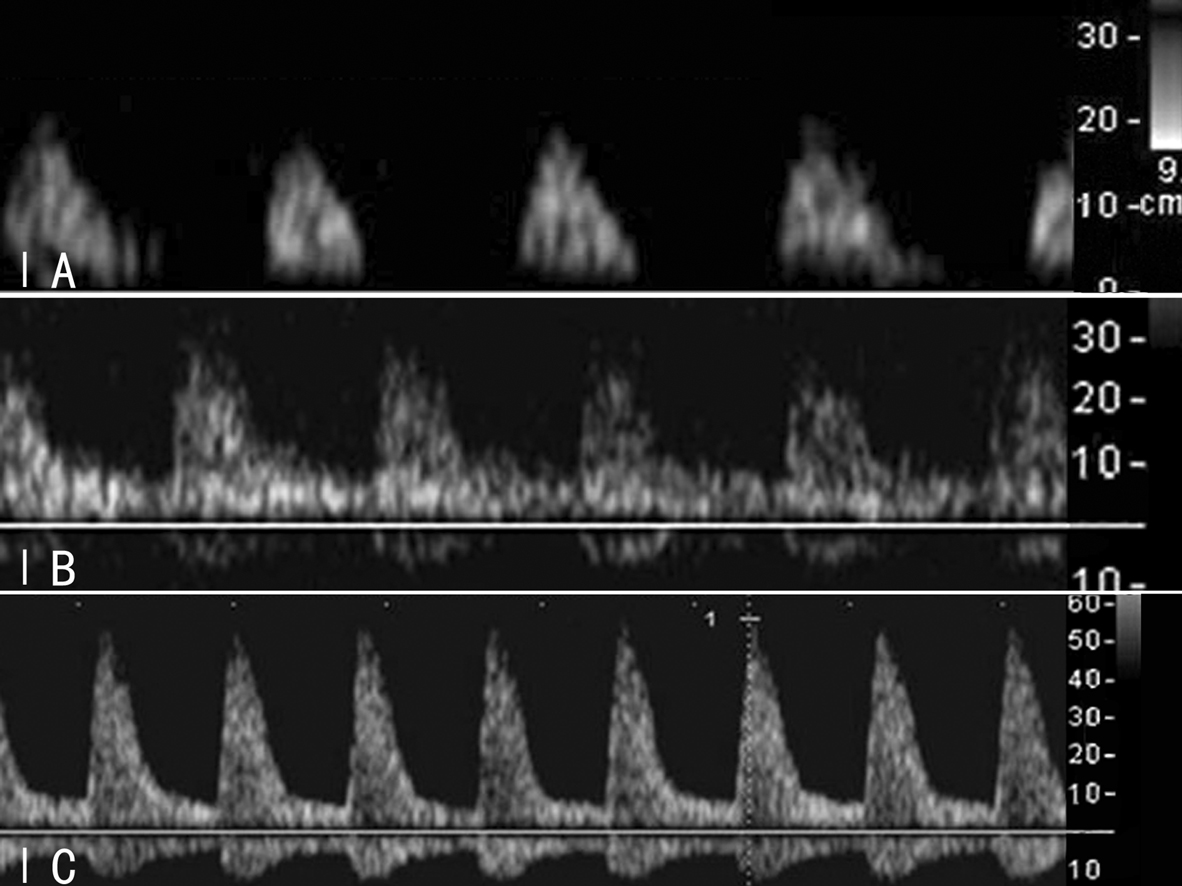

Sushil等将MCA频谱分为Ⅰ、Ⅱ、Ⅲ三种类型,其中Ⅰ型和Ⅱ型又分为A、B、C亚型(图2,3)。不同类型的MCA频谱具有不同的临床意义。

图2胎儿MCA多普勒血流速度曲线分型

图3胎儿MCA多普勒血流速度曲线亚型